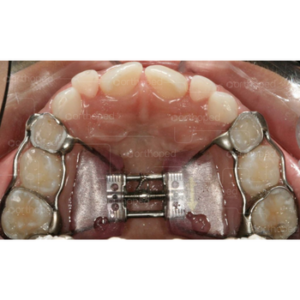

Diante do diagnóstico e indicação da expansão maxilar cabe ao profissional escolher o tipo de aparelho expansor assim como o protocolo de expansão a ser utilizado, certo? Claro que a escolha do tipo de aparelho também estará relacionada com a experiência clínica do profissional, além do embasamento científico para escolha do mesmo. E para mim, quando falamos em pacientes em crescimento, na grande maioria dos casos, a opção acaba sendo o expansor maxilar dentomucossuportado conforme preconizado por Haas. E diante da escolha do aparelho expansor, como orientar seu paciente nos cuidados com aparelho expansor fixo?

A instalação de um dispositivo ortodôntico fixo por si só já pode ser considerada como um fator retentor de placa e, portanto, os cuidados com a higiene devem ser criteriosos durante o uso do aparelho de expansão maxilar e devem ser reforçados no início do tratamento.

No caso do aparelho dentomucossuportado (com acrílico no palato), o uso de uma seringa descartável de 5 ou 10 ml pode auxiliar na limpeza conforme ilustrado na imagem abaixo. Peça para os pais encherem a seringa de água e limparem o aparelho com cuidado pelo menos uma vez ao dia.